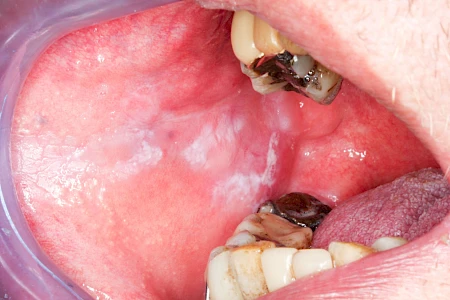

Speicheldrüsenzyste

Eine Speicheldrüsenzyste (Speicheldrüsenretentionszsyte) kann als Schwellung oder Auftreibung meist im Bereich der größeren Ausführungsgängen auffallen, wenn z. B. ein Speichelstein den Speichelfluss behindert. Vor allem bei den Mahlzeiten, wenn der Speichelfluss angeregt wird, nimmt die Auftreibung oder Schwellung schmerzhaft weiter zu. In der Regel ist die Unterkieferspeicheldrüse (Glandula sublinugalis) betroffen. Man spricht dann auch von einer Frosch- bzw. Fröschleingeschwulst (Ranula). Bringt sanftes Massieren der Schwellung bzw. Auftreibung keine Verbesserung, sollte ein Arzt oder Zahnarzt hinzugezogen werden